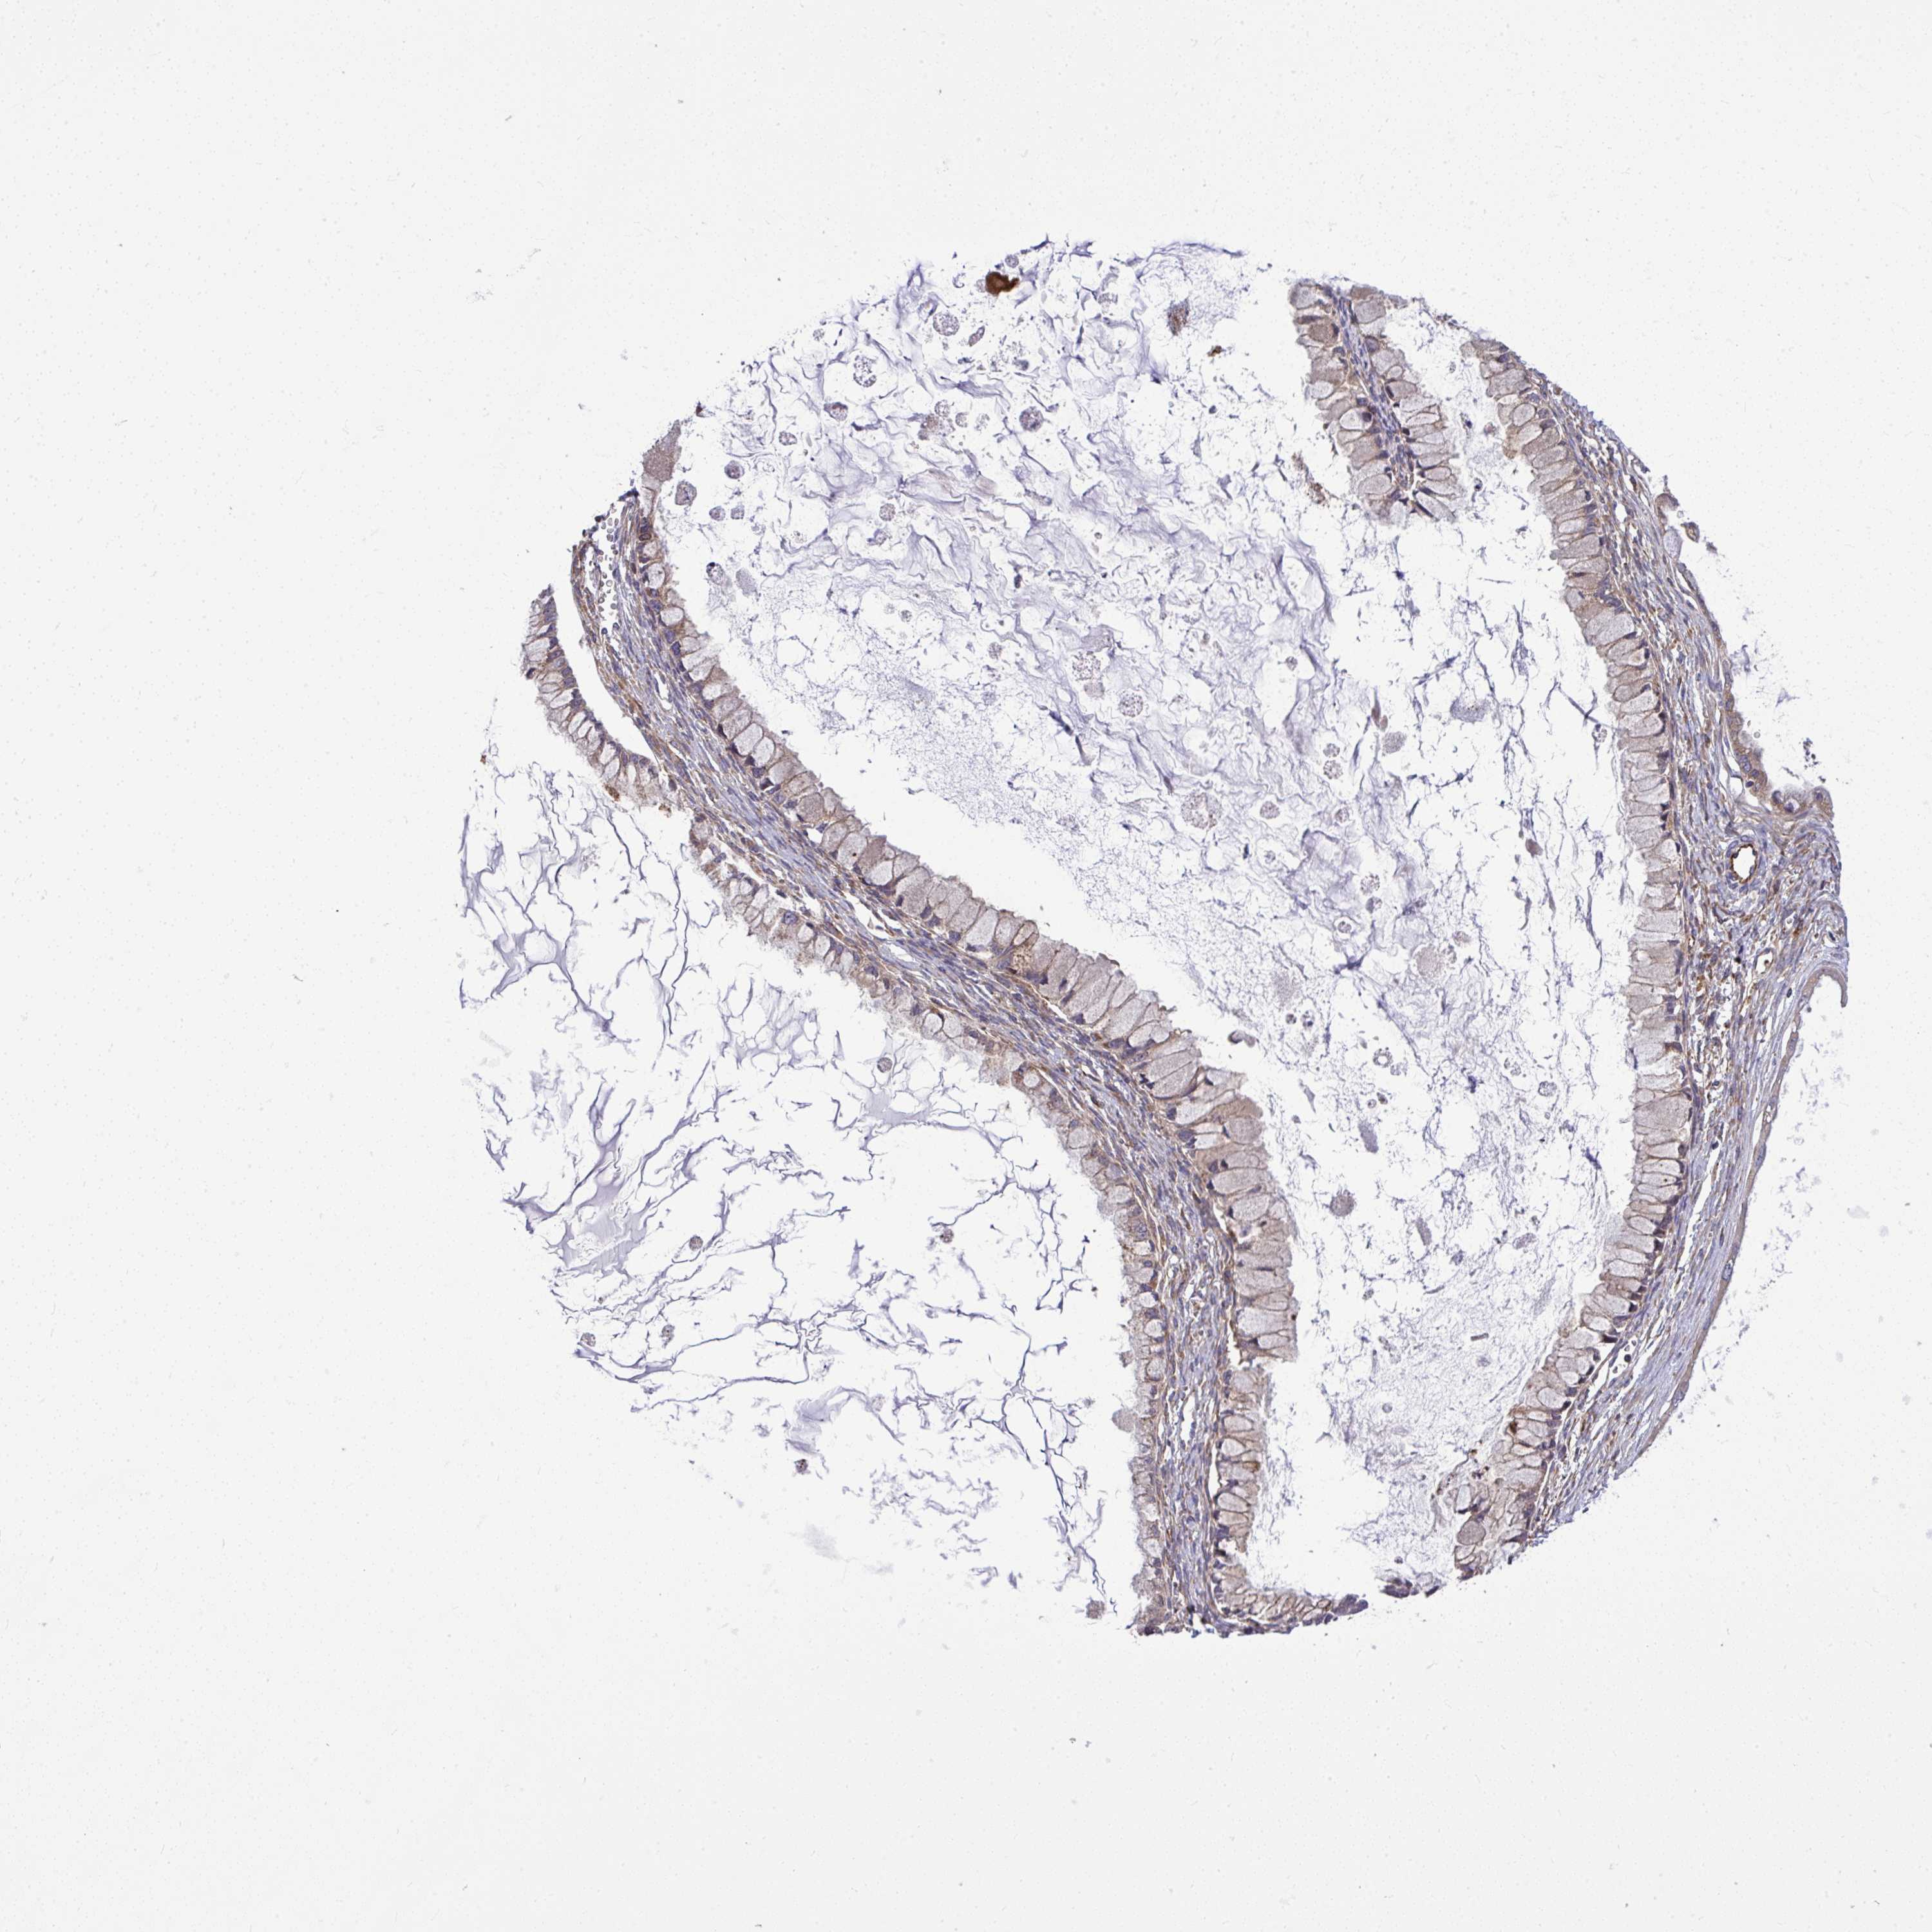

OVARIAN CANCER - Protein expressioni

A mouse-over function shows sample information and annotation data. Click on an image to view it in a full screen mode. Samples can be filtered based on level of antibody staining by selecting one or several of the following categories: high, medium, low and not detected. The assay and annotation is described here.

Note that samples used for immunohistochemistry by the Human Protein Atlas do not correspond to samples in the TCGA dataset.

Antibody stainingi

Antibody staining in the annotated cell types in the current human tissue is reported as not detected, low, medium, or high, based on conventional immunohistochemistry profiling in selected tissues. This score is based on the combination of the staining intensity and fraction of stained cells.

Each image is clickable and will lead to virtual microscopy that enables deeper exploration of all samples and also displays staining intensity scores, fraction scores and subcellular localization as well as patient and tissue information for each sample.

Antibody HPA035945

Antibody HPA056766

Antibody CAB037212

Cystadenocarcinoma, serous, NOS